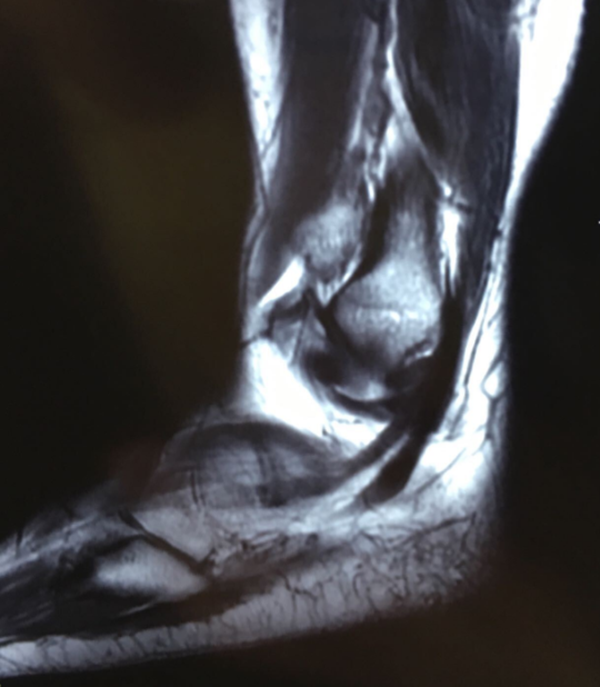

Xx,女,37岁,左踝关节内翻位扭伤10月余左踝关节疼痛肿胀活动障碍。

入院诊断:

左踝关节距腓前韧带跟腓韧带损伤;

左踝关节剥脱性骨软骨炎;

肌骨超声显示:左踝关节距腓前韧带部分断裂,跟腓韧带损伤。

图8 MR显示左踝关节距骨体剥脱性骨软骨炎,距腓前后韧带与跟腓韧带损伤